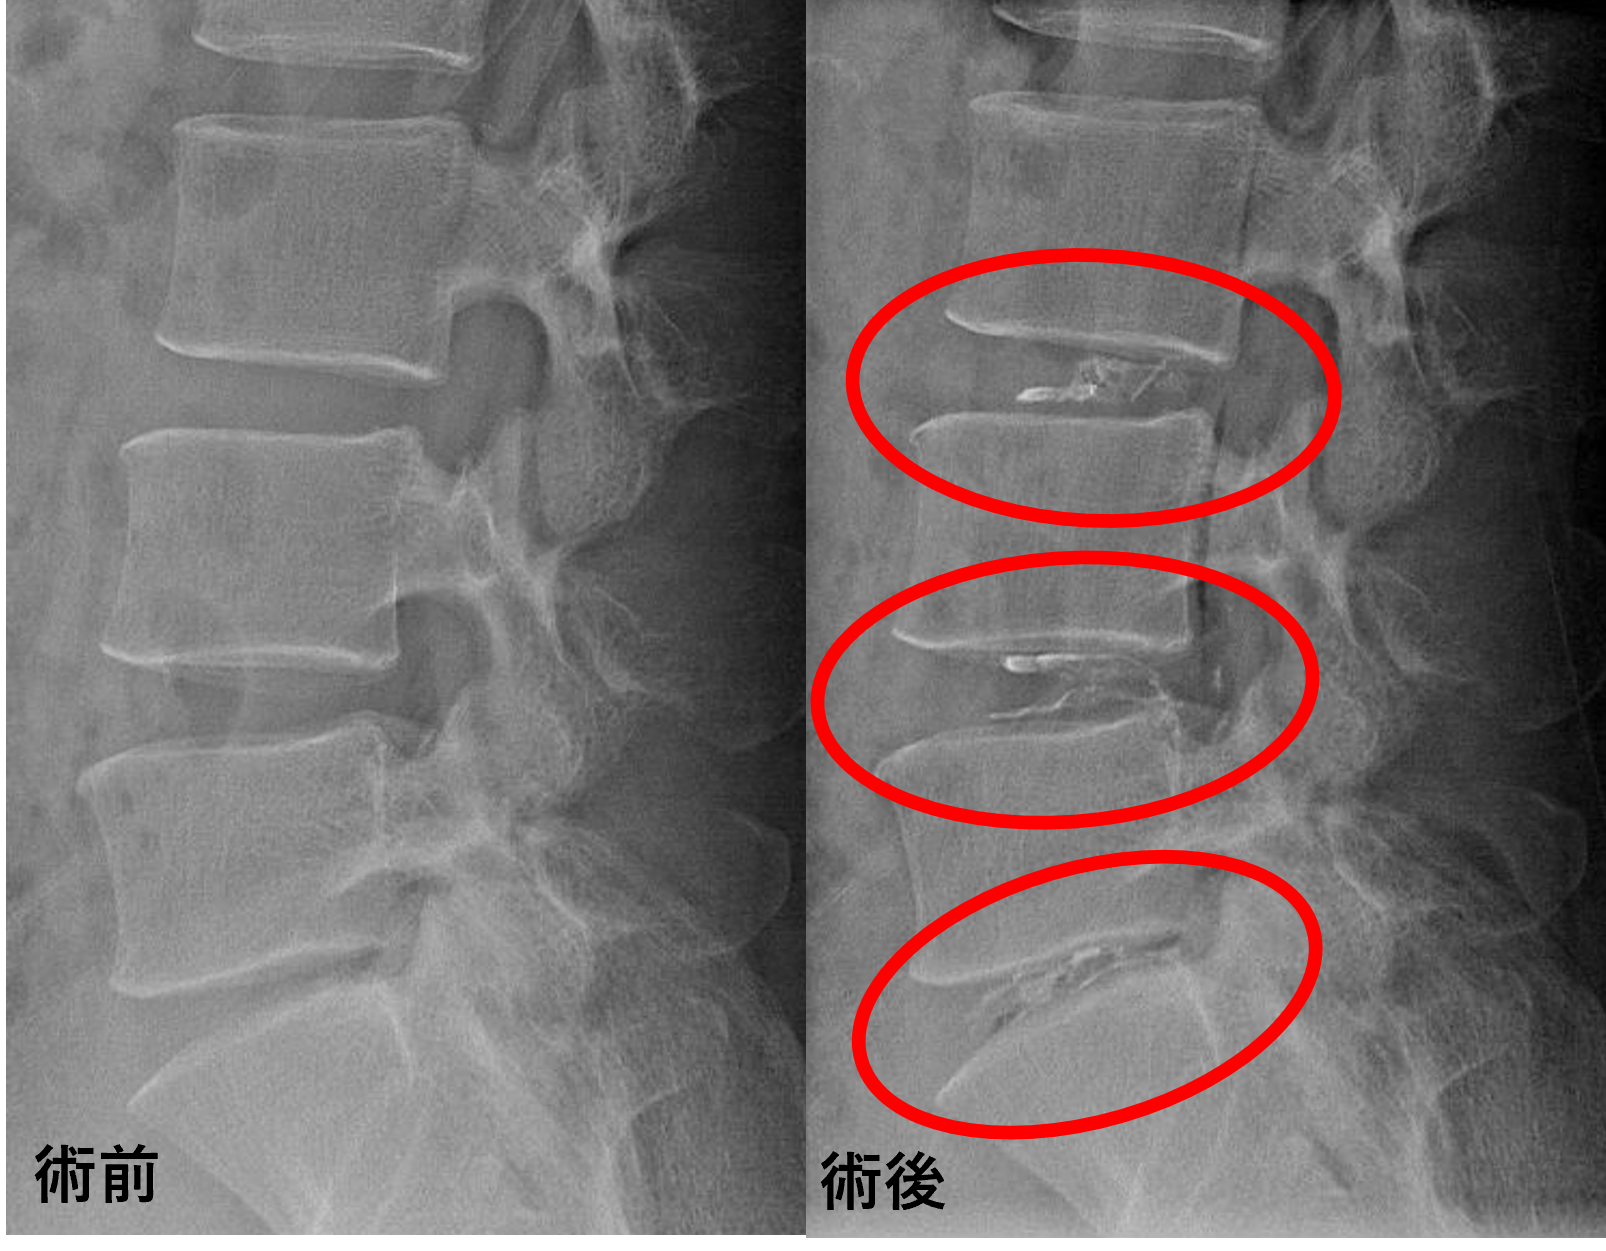

画像及び所見について

- L3/4、4/5 – 椎間板変性

- L5/s – 椎間板変性、膨隆、椎間孔狭窄、終板変性

以上のことが画像上認められました。

L3/4、4/5、5/sの椎間板所見による脊柱管の圧排が、症状の原因の可能性が高い。

患者様と相談の元、L3/4、4/5、5/sにセルゲル法を施行